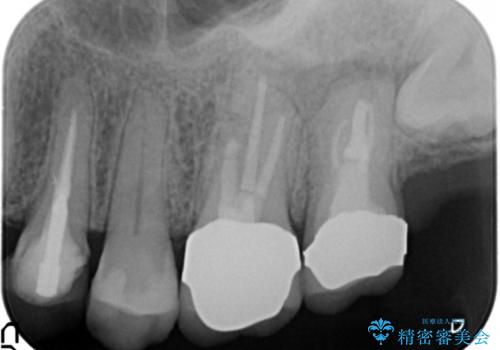

精査したところ、奥歯(左上67)の根尖部に位置した歯茎に瘻孔(膿の出口)ができており、CTを撮影し確認すると奥歯2本(左上67)の根尖病変は大きくつながっていました。

銀座しらゆり歯科の林院長による精密根管治療を受けて頂いたのち、メタルボンドクラウンによる補綴を行いました。